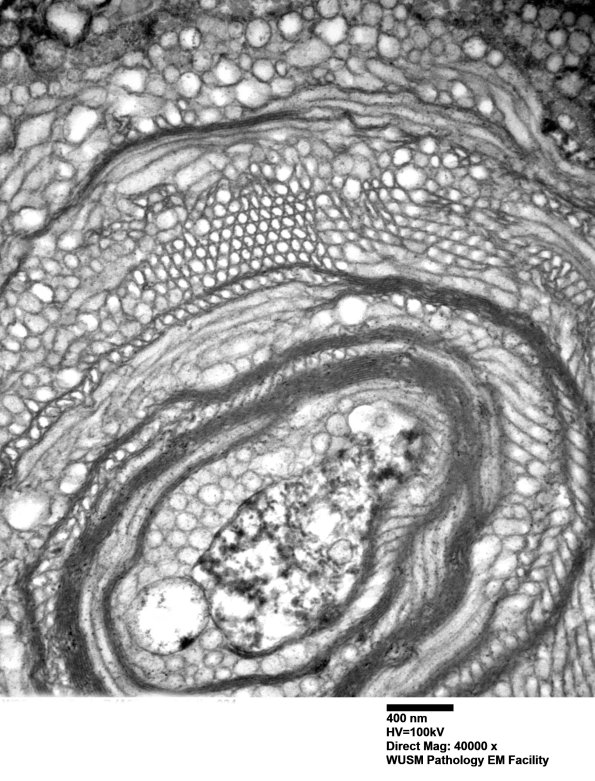

Two magnifications of an axon undergoing vesicular myelin change and axonal degradation. (electron micrographs)